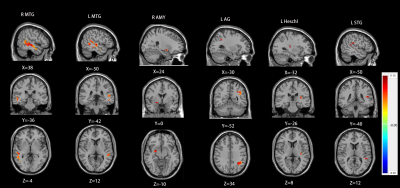

RESULTS: Compared with healthy controls, chronic tinnitus patients with hearing loss showed a significantly increased ALFF values in the right hippocampus, left middle temporal gyrus (MTG), left middle frontal gyrus (MFG), and bilateral precuneus, and a significantly increased ReHo values in left PAC, bilateral MTG, left superior temporal gyrus (STG), right amygdala and left angular gyrus (AG). Based on FC analysis, the left PAC showed reduced functional connectivity with non-auditory brain regions including the right MFG, right cingulate cortex, right cuneus and left cerebellum in the groups of chronic tinnitus with hearing loss compared with healthy controls.

Figure1 chronic tinnitus patients showed a significantly increased ALFF values in the right hippocampus, left MTG, left MFG, and bilateral precuneus